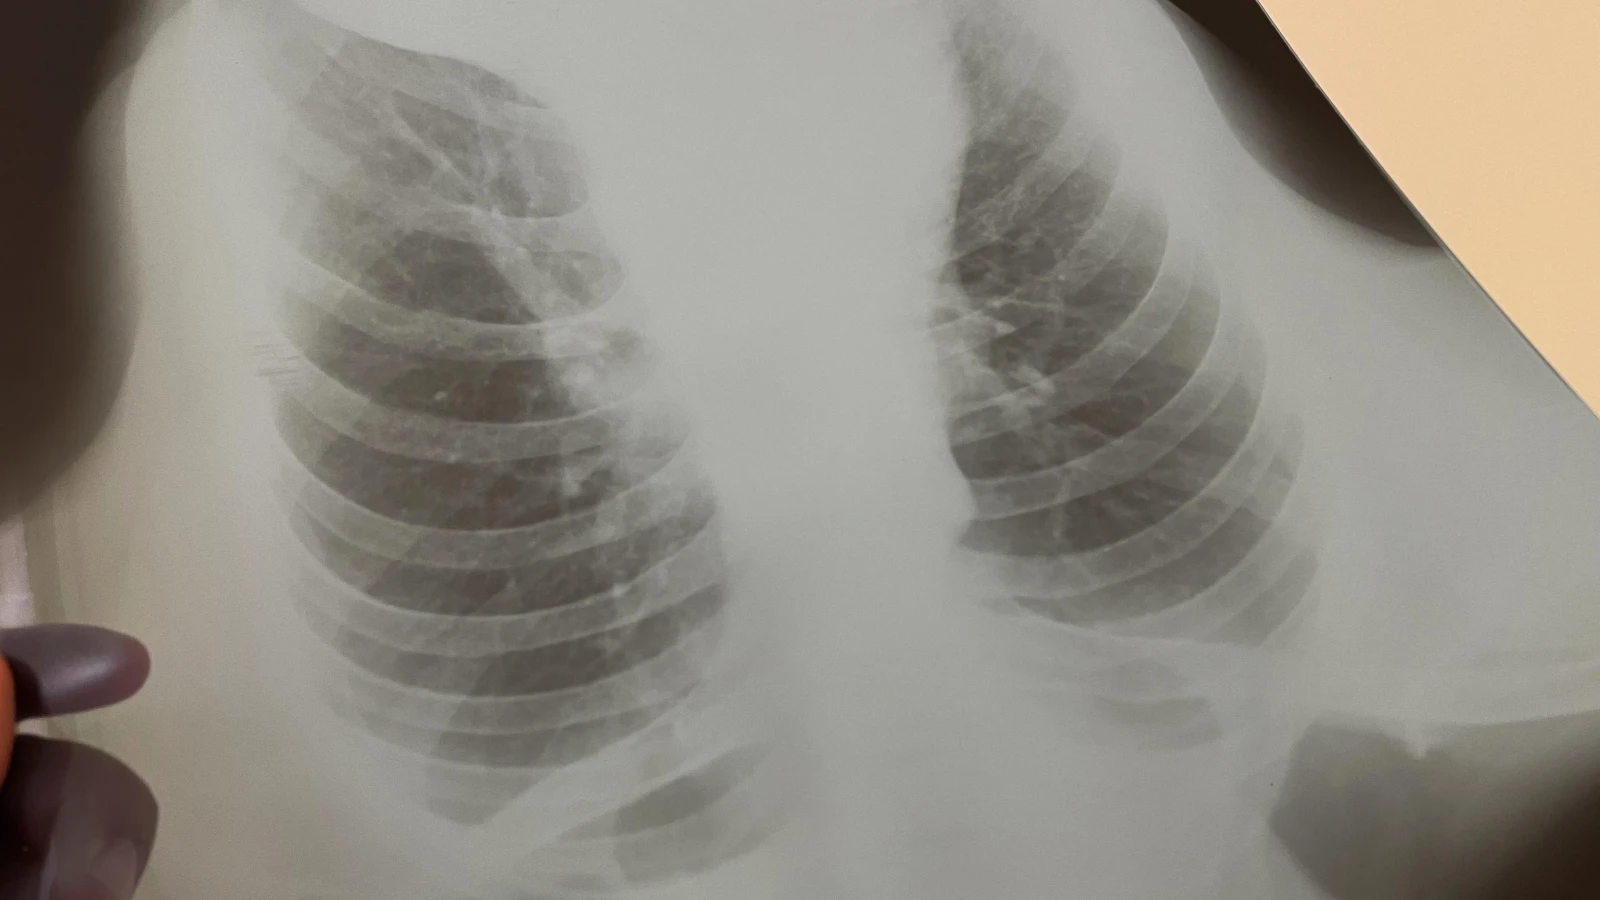

— Ждем всех желающих, вне зависимости от статуса застрахованности в системе ОСМС бесплатно пройти все методы выявления туберкулеза (тест GeneXpert, рентген снимок, результаты анализов), — сообщили в ведомстве.